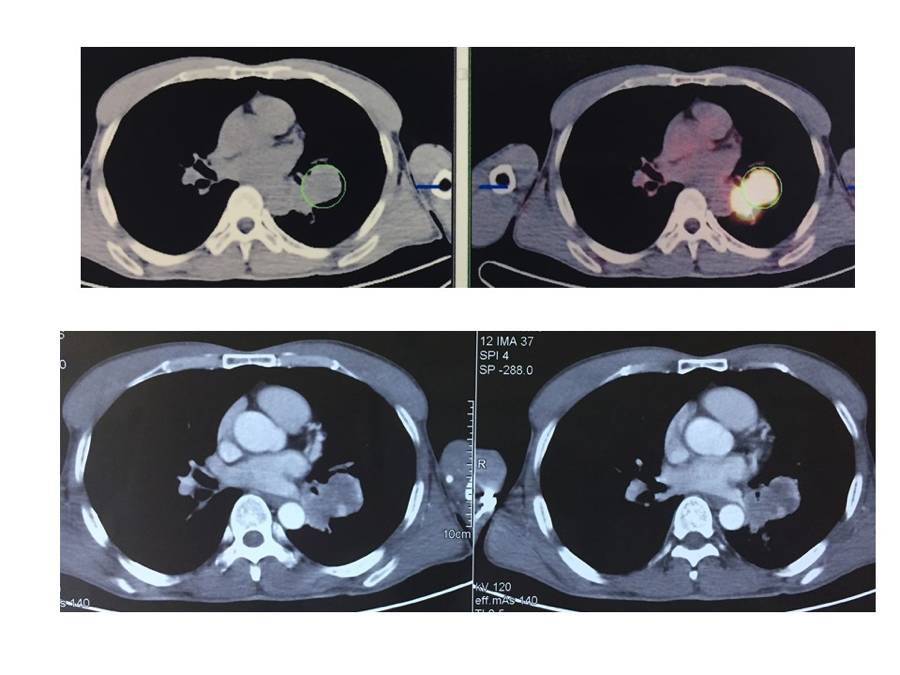

2017-9-20我院PET/CT示:左肺下叶背段支气管断端肿物,大小约4.1X4.1X3.0cm,糖代谢增高,考虑中央型肺癌;相邻左侧叶间肿大淋巴结,糖代谢增高,考虑转移性淋巴结;左肺下叶背段模糊片影糖代谢稍增高,考虑阻塞性肺癌。

目前诊断:左肺中央型鳞癌cT2bN1M0 IIB期

初治患者,诊断:左肺中央型鳞癌cT2bN1M0 IIB期(ALK阴性,PD-L1 90%)